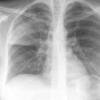

Case 2 Lingular pneum PA

Date: 04/17/2005

Views: 6415